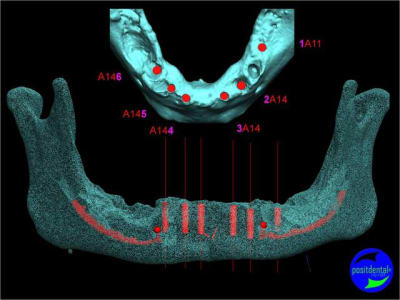

Extraction, pose d’implants Ankylos, pose des piliers Standard définitifs, mise en charge immédiate bi-maxillaire en une chirurgie.

Maxillaire supérieur – extraction 13, 26, 7 implants en MCI, 1 implant en MCR pose summeurs, densification par ostéotme, comblement osseux, bridge provisoire sans fausse gencive avec renfort métallique.

Maxillaire inferieur – extraction 35, 34, 44, 45, 6 implants MCI, comblement osseux, bridge provisoire sans fausse gencive avec renfort métallique.

en attendant la pano voici les coupes de la S.I.A.O.

bien...mais dans certaines zones,surtout postérieures, j'aurais mis plus gros...surtout qu'il y a la place...